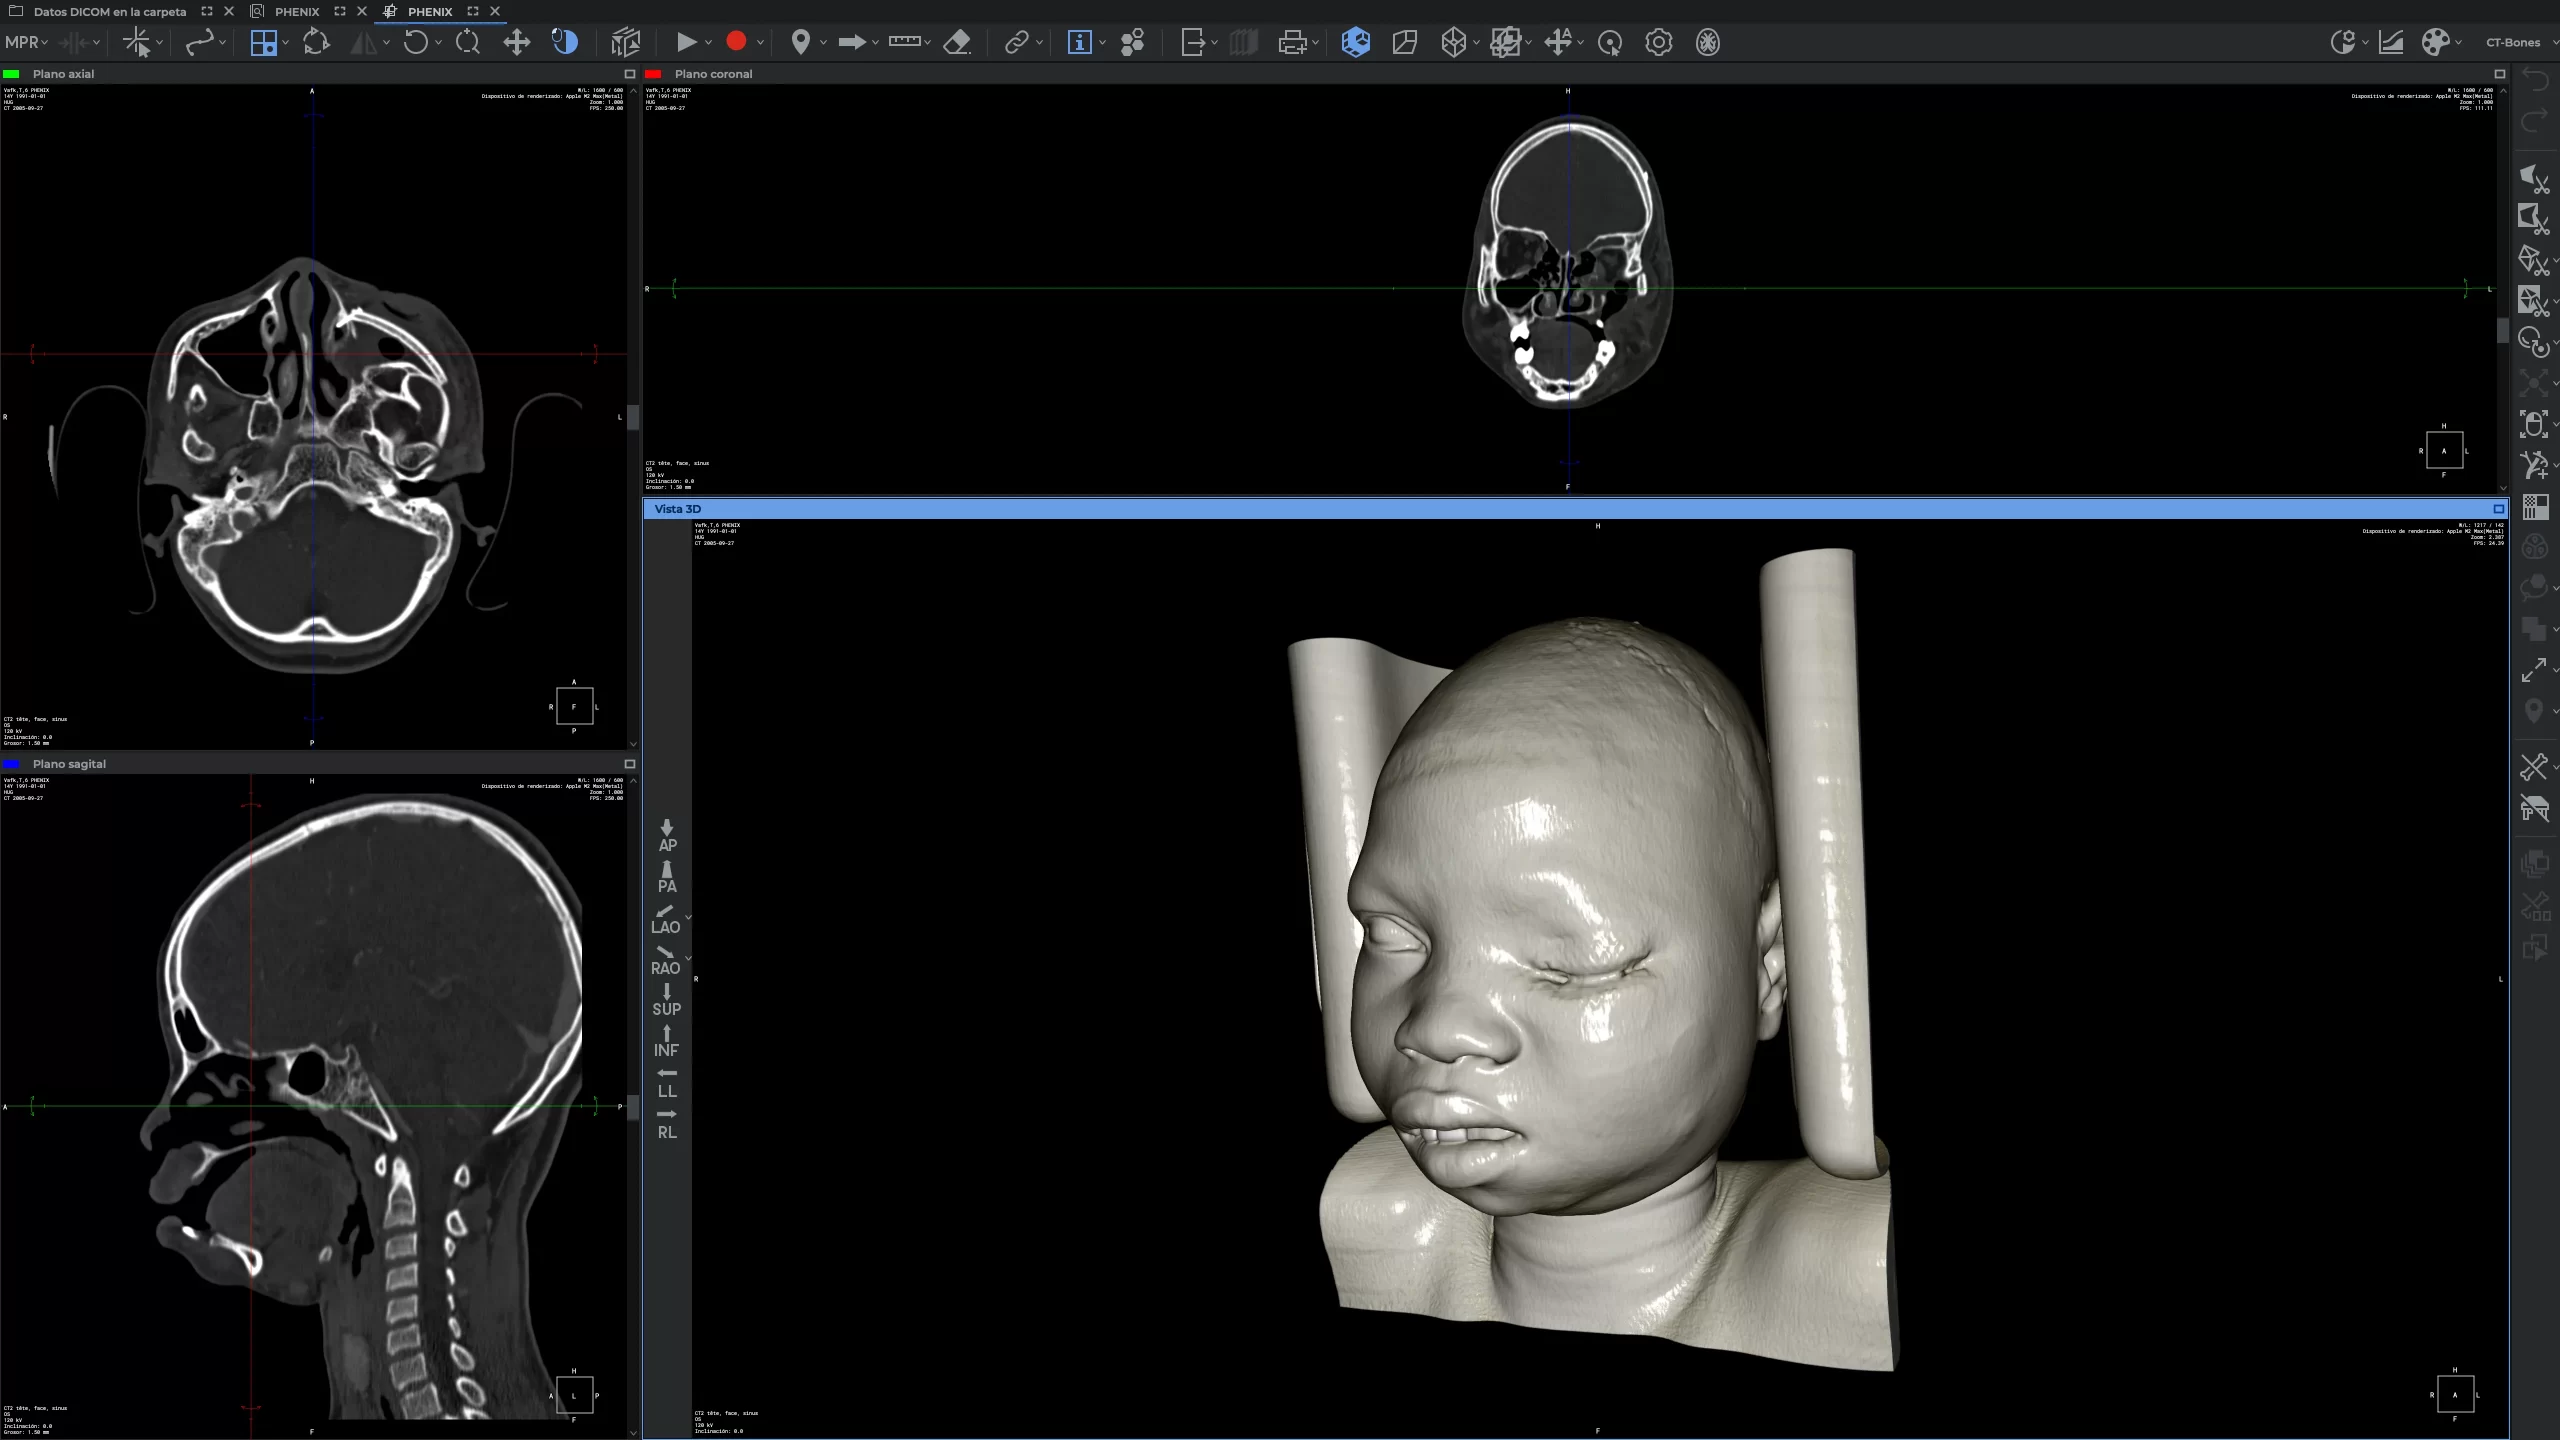

SIT Anatomy

La mesa SIT Anatomy es una solución versátil de alta tecnología con modelos 3D basados en cadáveres reales y renderizados foto realísticamente. Ofrece:

Visualización de imágenes DICOM y PACS

Estudio morfofuncional con correlación clínica